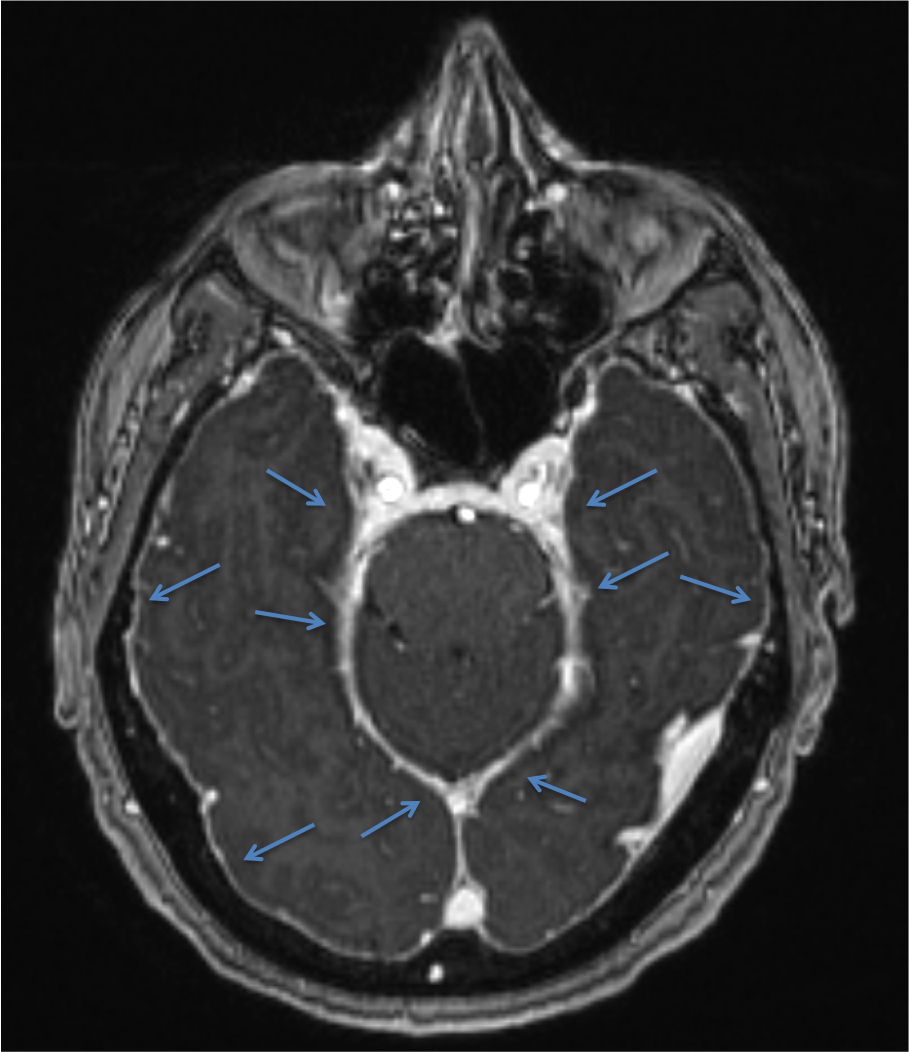

En la Imagen 6 y 7, se pude observar la captación dural de contraste que se debe a la mayor concentración de contraste (gadolinio) en la vasculatura y fluido intersticial de la duramadre. Esta hipercaptación afecta a la duramadre (paquimeninge) y no a las leptomeninges (aracnoides y piamadre) por lo que no afecta a la profundidad de los surcos corticales ni alrededor del tronco cerebral, es continuo no nodular y afecta a los compartimentos supra e infratentorial. En la Imagen 1 se observa también el engrosamiento dural sin contraste en fosa posterior y primeros segmentos cervicales.